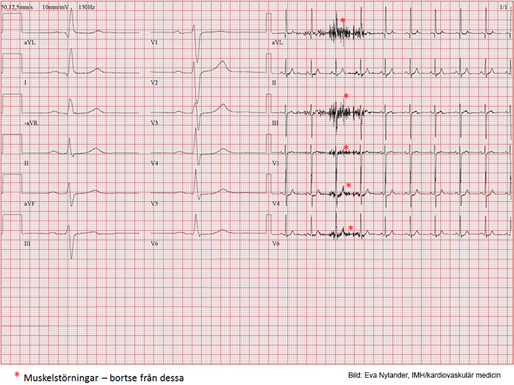

Vad kan du utläsa av detta?

Angina pectoris

I vila inga ST- T- förändringar. Under arbete ses en successivt ökande ST- sänkning över vänster kammare (tyder på koronar insufficiens). Sänkningen är platåformad och uppgår till mer än 2 mm (0.2 mV) i V5 och V6 på högsta belastningen (men ses ju även under II och aVF). Efter arbete går ST- sänkningen i regress men 6 minuter efter arbetet ses en accentuerad formförändring och T- negativitet i vänstersidiga bröstavledningar. EKG-reaktionen är patologisk och är förenlig med coronarinsufficiens.